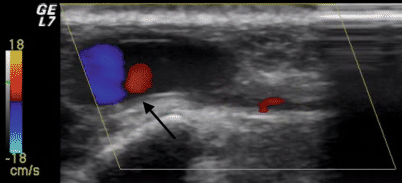

Die Diagnose eines Pseudoaneurysmas der A. ulnaris wurde in einer farbkodierten duplexsonographischen Ultraschalluntersuchung während des Ambulanzbesuchs gestellt. Das Farbdopplerbild zeigte das typische „Yin-Yang“ Zeichen (Abb. 2). Die Indikation zur Rekonstruktion wurde aufgrund der Ischämie und der Behinderung bei der Berufstätigkeit gestellt. Nach zwei Wochen erfolgte die Aufnahme und am selben Tag wurde eine Angiographie zur Operationsplanung durchgeführt, welche ein Pseudoaneurysma der A. ulnaris mit Verschluss des oberflächlichen Handbogens zeigte (Abb. 3).

Abb. 2

Farbdopplerbild zeigt das typische „Yin-Yang“ Zeichen (Pfeil) im Pseudoaneurysma der A. ulnaris